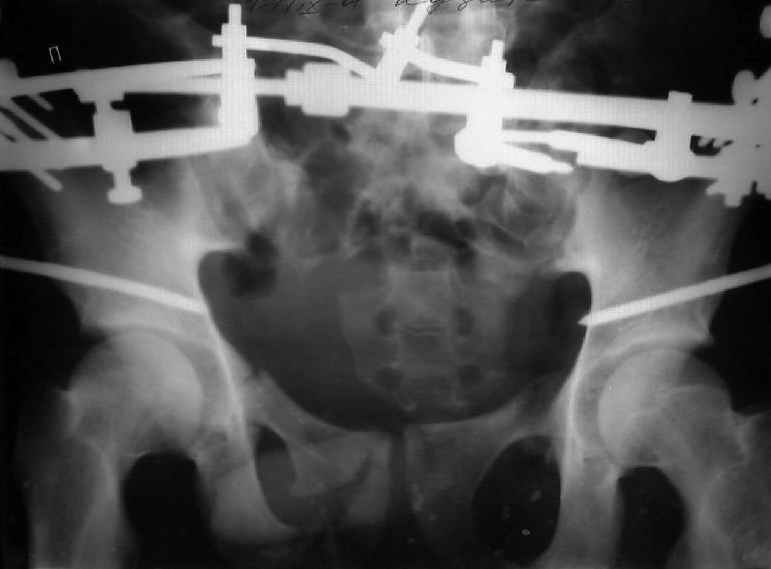

Re: Застарелый перелом таза

Для информации к размышлению о возможности исправления имеющейся деформации предлагаю похожий случай.